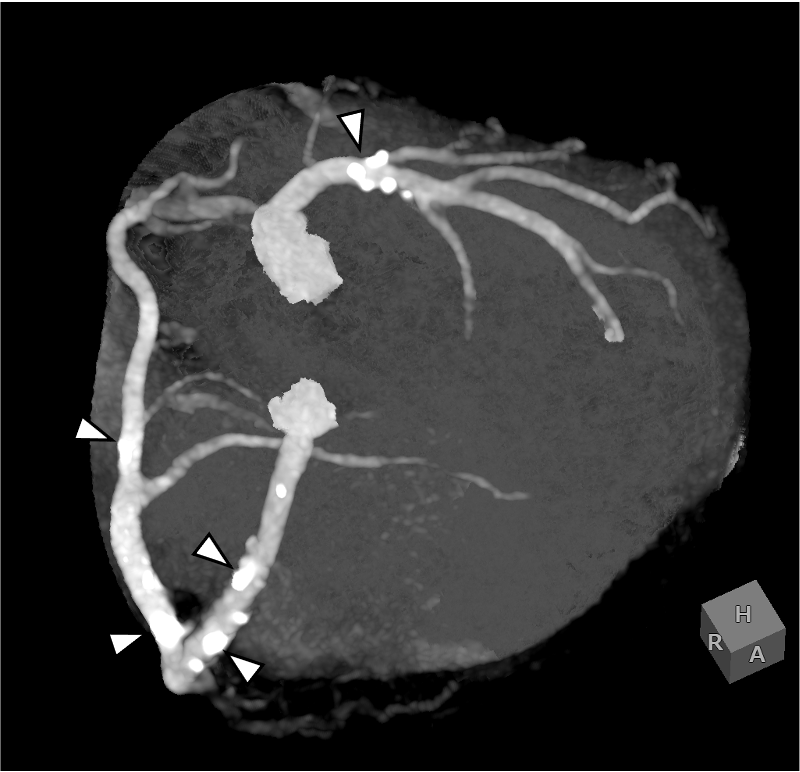

図2.volume rendering (VR)画像

前下行枝(LAD)は末梢まで描出されている. 回旋枝(LCX)は低形成である(矢頭).